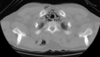

22

TC ventana mediastínica

Permite diferenciar las estructuras mediastínicas entre sí, pero el parénquima pulmonar aparece todo negro, sin apenas trama broncovascular.